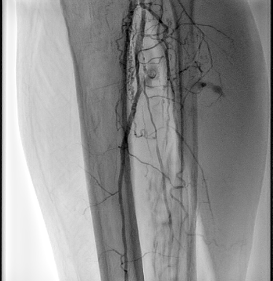

Пораженная подколенная артерия |

Окклюзия артерий голени |

- Следующим этапом выполнена механическая реканализация и баллонная ангиопластика артерий голени.

Ангиографическая картина голени перед баллонной ангиопластикой |

| Ангиографическая картина после баллонной ангио пластики | |